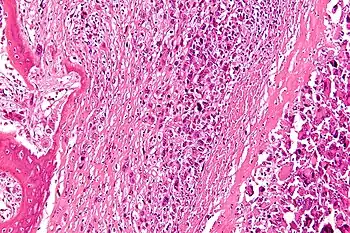

Diagnosis is generally by X-ray and other radiological tests such as CT scan, MRI, PET scan and bone scintigraphy.[4] Blood tests might include a complete blood count, inflammatory markers, serum electrophoresis, PSA, kidney function and liver function.[4] Urine may be sent for Bence Jones protein.[4] For confirmation of diagnosis, a biopsy for histological evaluation might be required.[4][2]

Diagnosis

A bone tumor may be felt on examination, following which a plain X-ray is usually carried out.[4][13] Imaging is interpreted with the location of the lesion and the person's age being taken into account.[14]

Blood tests might include a complete blood count, inflammatory markers, serum electrophoresis, PSA, kidney function and liver function.[4] Urine may be sent for Bence Jones protein.[4] Other tests that might be requested include a CT scan, MRI, PET scan and bone scintigraphy. For confirmation of diagnosis, a biopsy for histological evaluation might be required, using either a needle or by incision (open biopsy).[4][2]